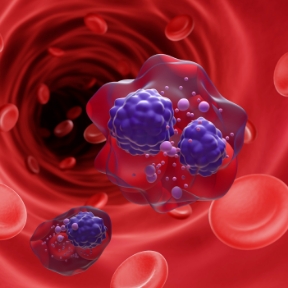

뼈 강화 효과가 입증된

신바로한약

골다공증으로 인해 파괴된 뼈

정상 수준으로 회복